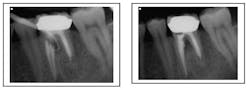

Transportations can be a result of a ledge formation. It is a false canal that does not follow the natural root anatomy. Unless there is a second canal, as in the mesial root of an upper molar or distal root of a lower molar, the chance of regaining access to the true canal is minimal. If these cases fail, they are best treated by extraction or a combination of retreatment and surgery, as is discussed below. (Wong, 1997)Strip perforation (coronal third of root) repair with MTA. Patient had a draining sinus tract into furcation. With perforation repair, sinus tract healed.